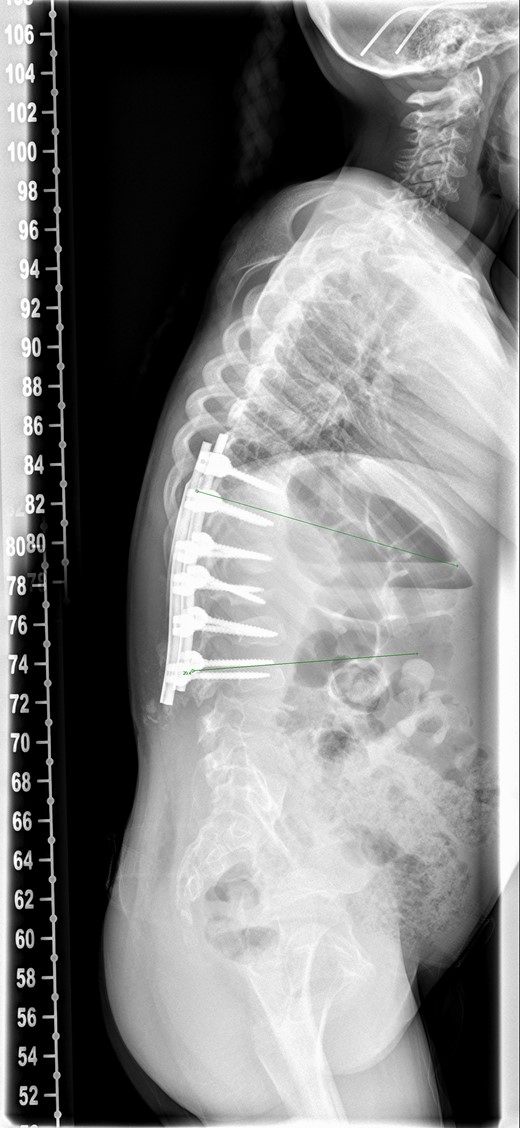

There was serous discharge with flakes of i-Factor in the drain postoperatively. Wound drain was removed on the second day and postoperative radiograph (Fig. 2) was satisfactory. Patient was discharged with a dry wound on the fifth day. Patient reattended hospital on seventh day with serous discharge from the drain site. There was no sign of infection and the wound was covered with a PICOTM dressing (Smith and Nephew), a negative pressure wound therapy system. At Day 10 the primary wound was healed, but serous fluid containing i-Factor flakes noted from the drain site. Patient was not started on antibiotics as there was no sign of infection and blood markers were normal. Wound was kept covered with a dressing and the discharge stopped.